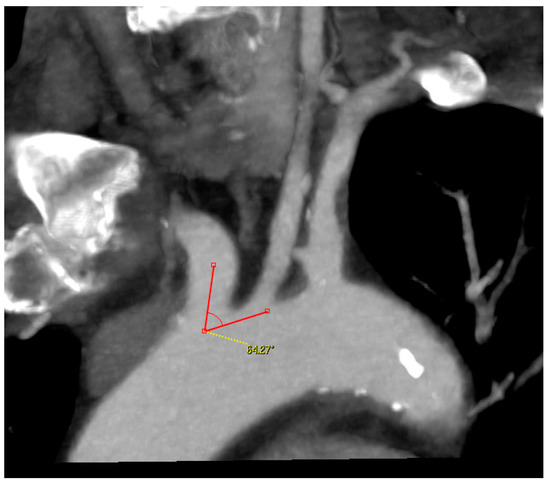

- Angle between the AA and the supra-aortic vessel: measured on the treated side only, through a multiplanar reconstruction and visualization of the AA in coronary and left anterior oblique (LAO) projection. One arm of the angle was drawn along the outer curvature of the AA and the second arm was placed in the middle of the CCA or brachiocephalic trunk. The right-side angle was chosen for selection criteria (Figure 3);

Figure 3. Angle measurement between the aortic arch and supra-aortic vessel.

Type II AA was found 20% more frequently than type I AA. The angle between the AA and the supra-aortic vessel varied depending on the type of AA and the side of the lesion. Type I AA and right-sided lesions were associated with larger angles, whereas type II AA and left-sided lesions were associated with smaller angles.

The perioperative incidence of stroke and death was lower in this study than in the RCTs that compared CAS against CEA for both symptomatic and asymptomatic patients. Based on our results, anatomical criteria should be taken into account when determining the indication for CAS. For cannulating the CCA, the angle between the AA and the supra-aortic vessel, as well as the AA-type, play very important roles. The AA changes over time, and these changes are caused, among other things, by atherosclerosis, arterial hypertension, and age. AA remodeling results in elongation of the AA and caudal positioning of the supra-aortic vessels [20]. At the same time, the difficulty of cannulating the supra-aortic vessels increases parallel to the AA-type, and simultaneously with an increased risk of embolization due to the required manipulations in the AA [21,22]. In our institution, a type III AA is considered a contraindication for transfemoral cannulation of the carotid artery.

The remodeling changes in the AA cause a variation in the angle between the AA and supraaortic vessels. Based on the available literature on this topic, it is still currently not possible to recommend an exact angle for CAS. Suh et al. reported that the angle between the AA and CCA is significantly smaller on the left side than with the brachiocephalic trunk. The left CCA originates from the AA and has an oblique course from right to left and from caudal to cranial. On the other hand, the CCA to the right side has a much straighter course [23]. We have generally treated moderate-grade angles, with no obtuse or acute angles. It was particularly interesting in this study that the angle on the left side was 10° smaller than on the right side. This confirms the assumption of Suh, G.Y. and is a possible explanation for why left-sided supra-aortic interventions are technically more difficult and are associated with higher complication rates [24,25]. Our results also showed that the angle of the type I AAs were greater than the type II AAs.